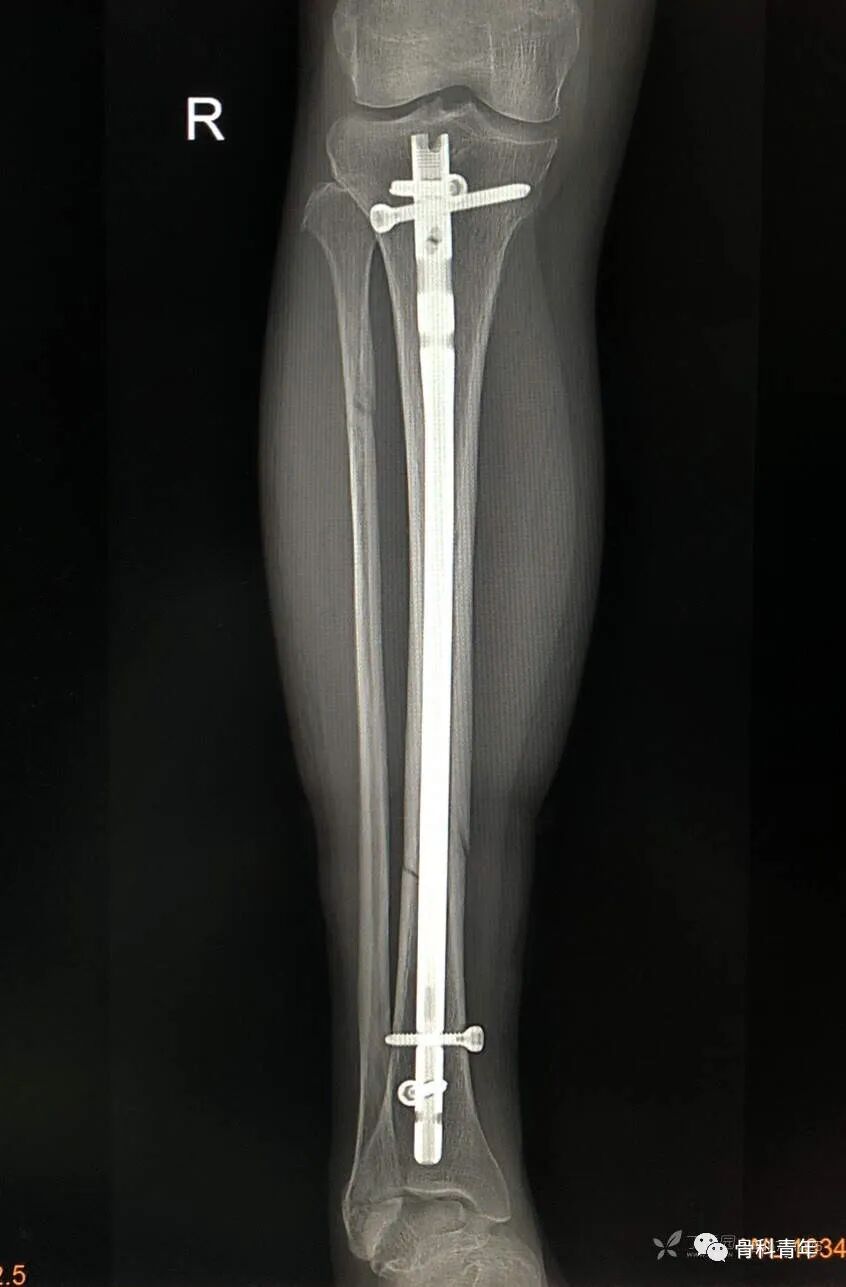

9.胫骨骨折(髓内钉)